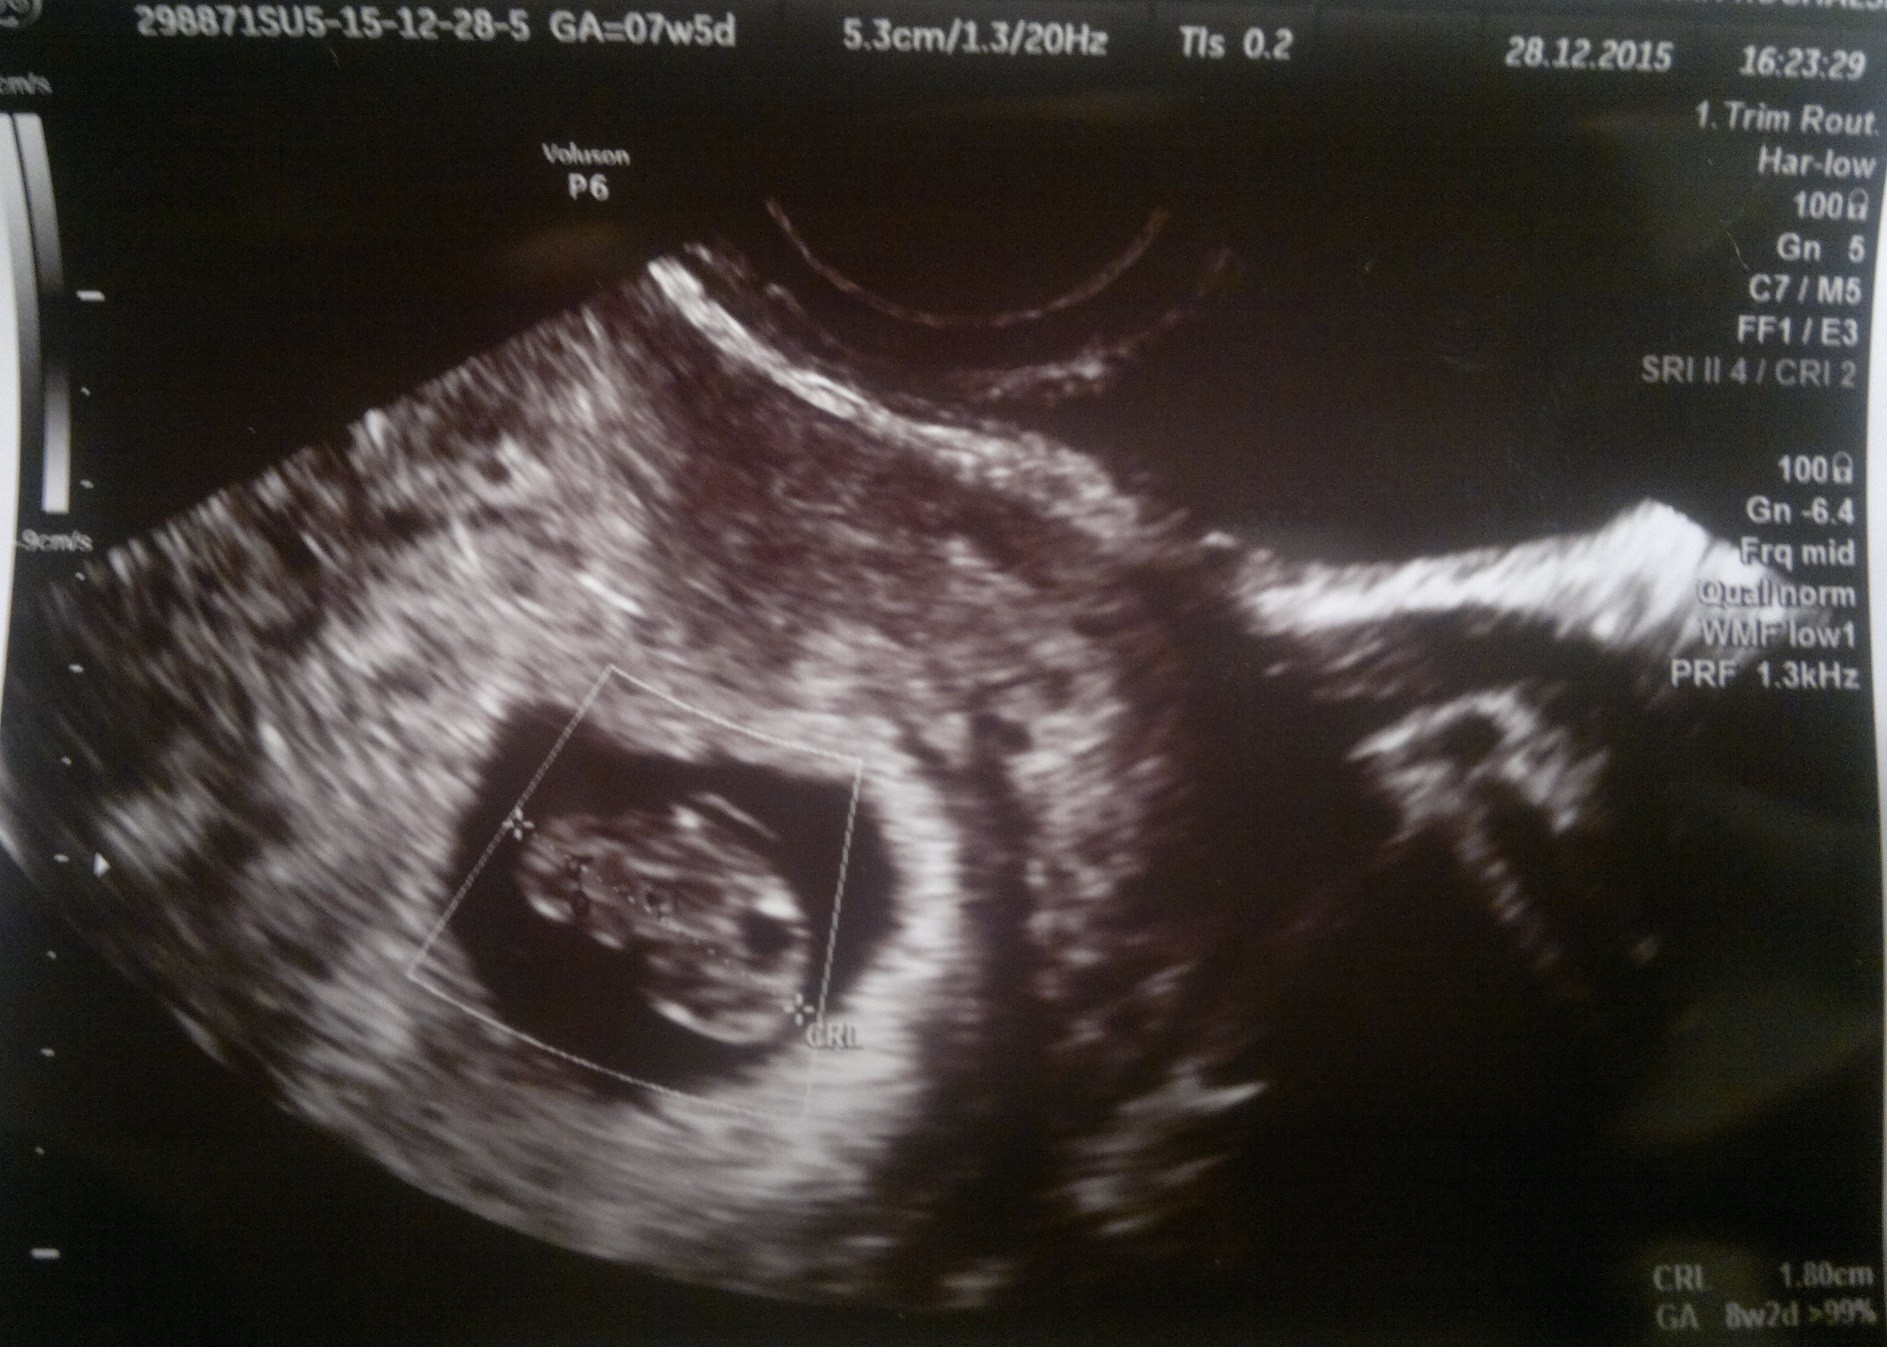

I JEEEEEEEST!!!! Jest nasz mały człowieczek z bijącym serduszkiem. Tego co czułam przed wizytą nie potrafię nawet przyrównać do najgorszego egzaminu- ogromny stres ( Przypomnę tylko, że dwa razy przechodziłam już łyżeczkowanie po pustym jaju płodowym, więc podświadomie nastawiałam się na najgorsze)

Od ostatniej miesiączki mija u mnie 7t5d, a z usg wiek ciąży wyszedł na 8t2d, termin lekarz wyliczył na 11 sierpnia.